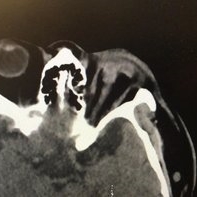

Ruptured globe on CT

Nov 19 2022 by Gareth Lema, MD, PhD

Runner meets park bench. The worst open globe I have ever seen on a CT scan. Multiple attempts at repair were made but the final visual acuity was light perception.

Photographer: Gareth Lema, MD, PhD, New York Eye and Ear of Mount Sinai

Imaging device: CT Scan

Condition/keywords: CT scan, open globe injury